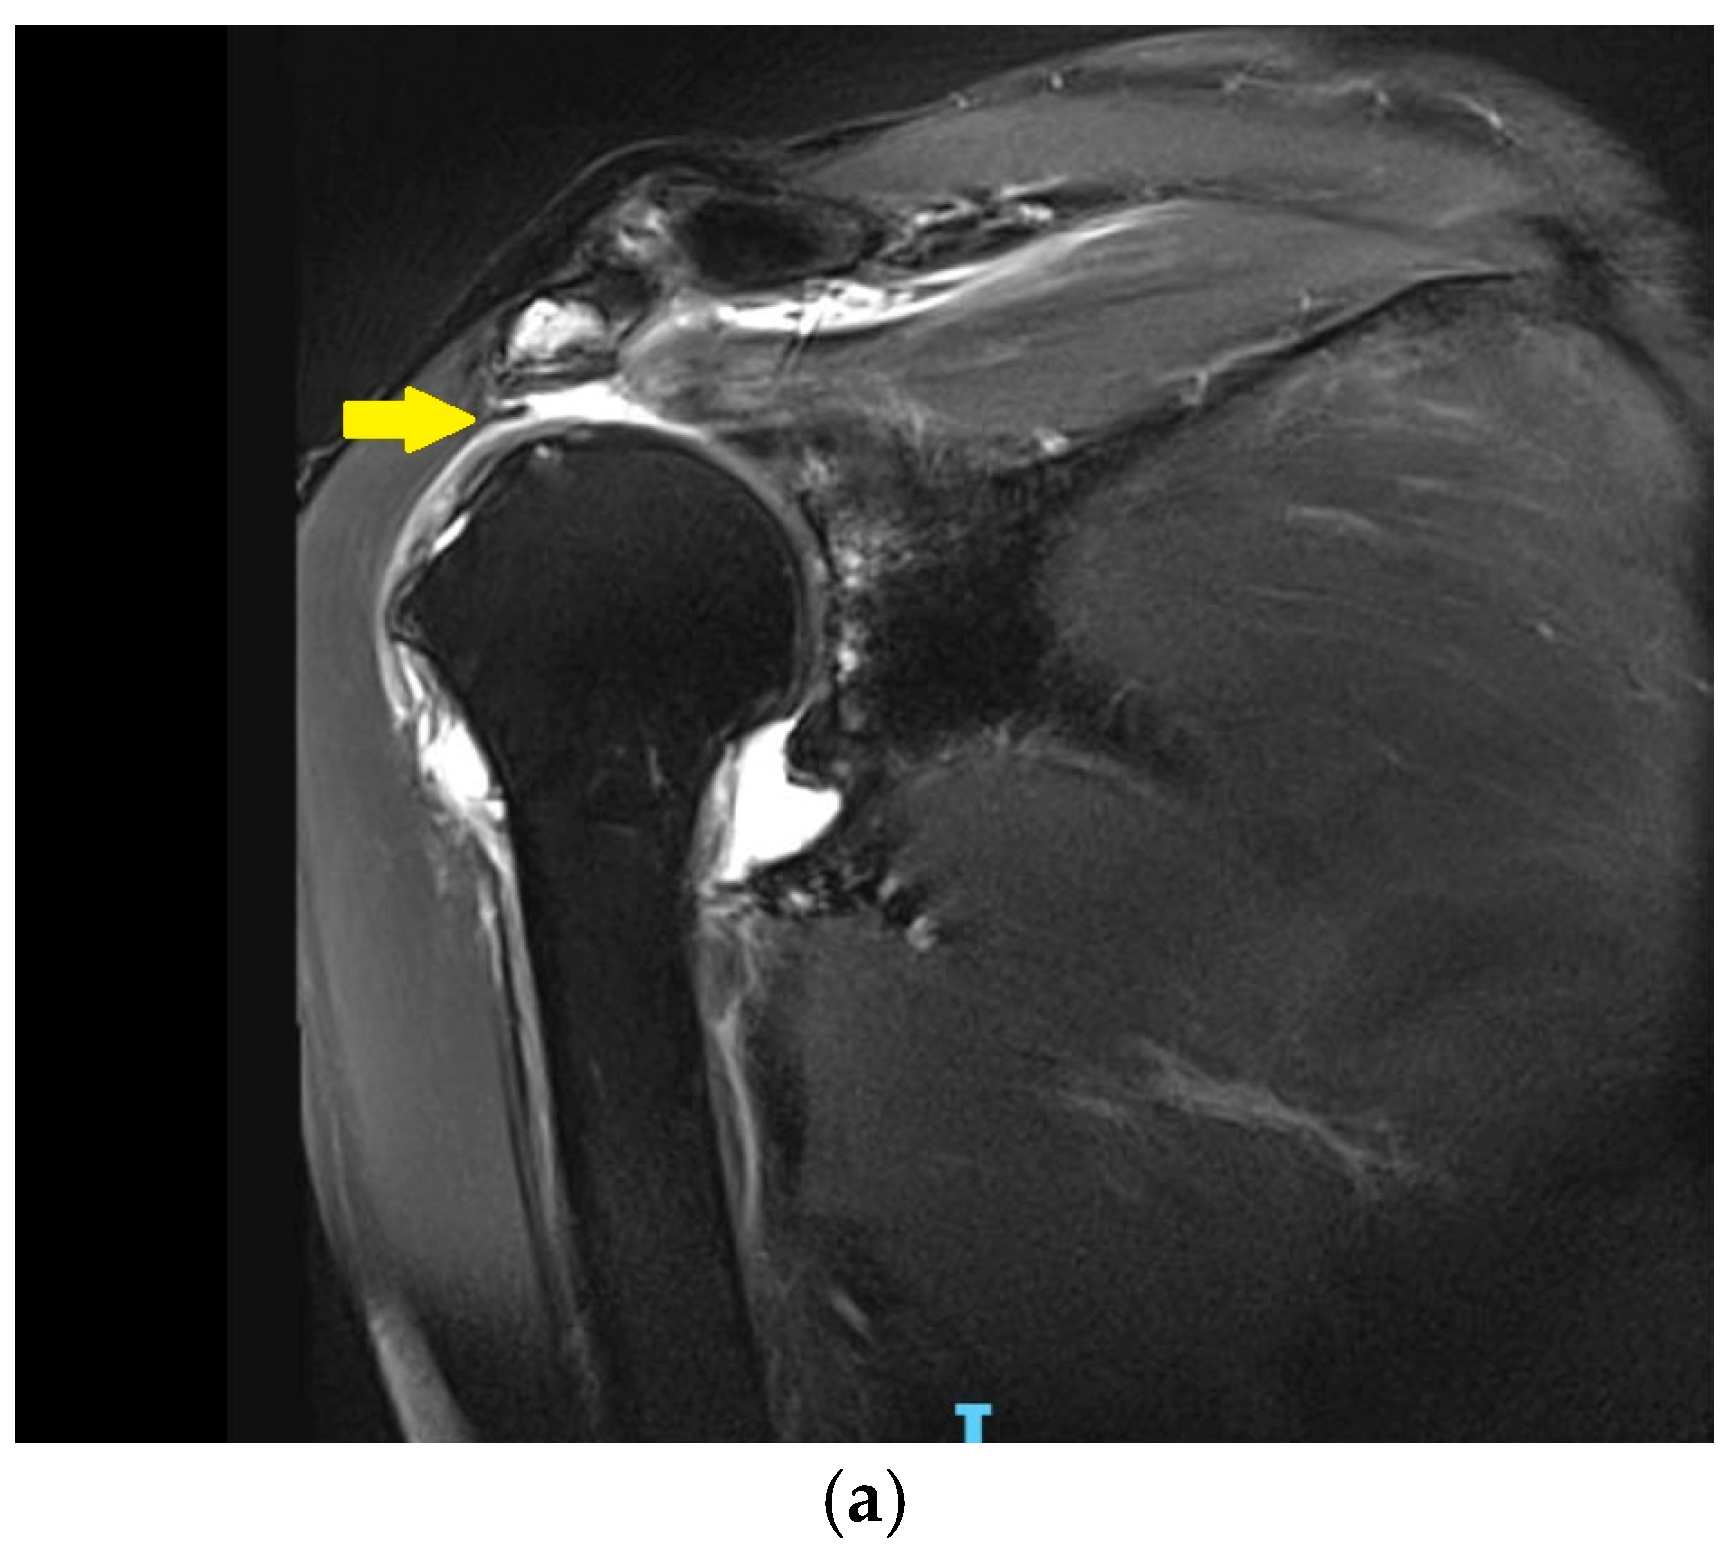

3.3. Irreparable Rotator Cuff Tears and Rotator Cuff Arthropathy